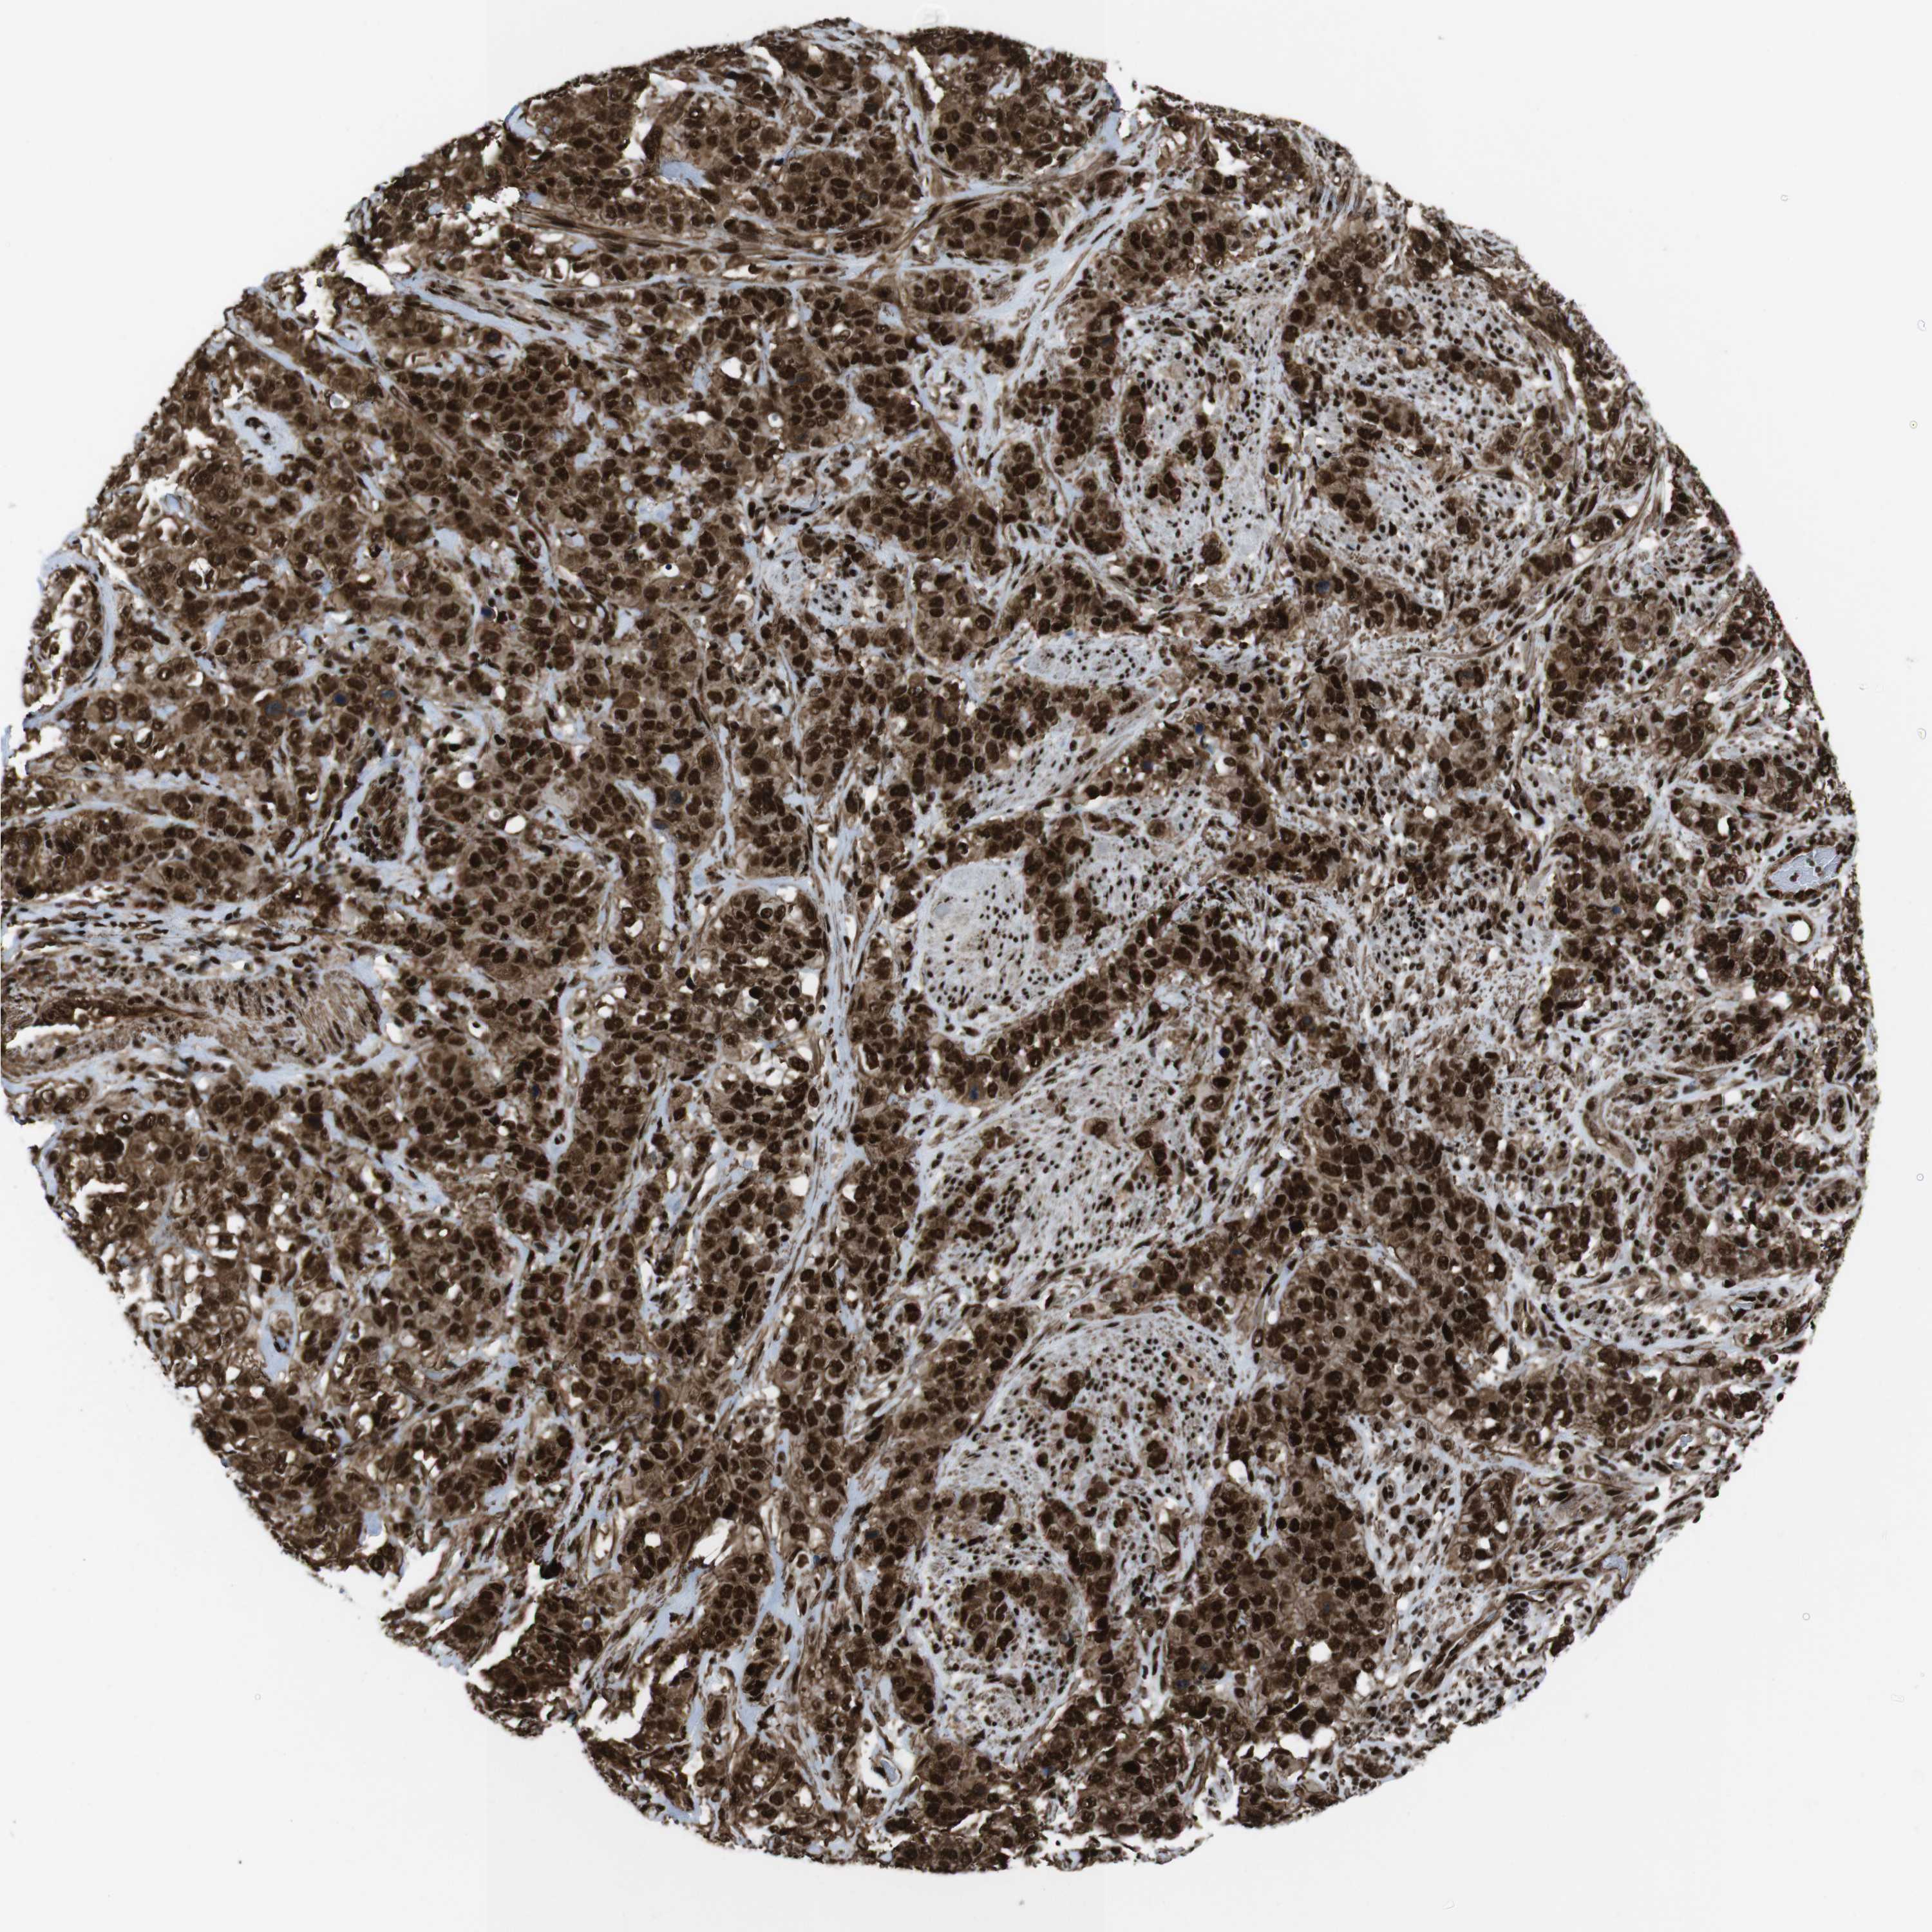

STOMACH CANCER - Protein expressioni

A mouse-over function shows sample information and annotation data. Click on an image to view it in a full screen mode. Samples can be filtered based on level of antibody staining by selecting one or several of the following categories: high, medium, low and not detected. The assay and annotation is described here.

Note that samples used for immunohistochemistry by the Human Protein Atlas do not correspond to samples in the TCGA dataset.

Antibody stainingi

Antibody staining in the annotated cell types in the current human tissue is reported as not detected, low, medium, or high, based on conventional immunohistochemistry profiling in selected tissues. This score is based on the combination of the staining intensity and fraction of stained cells.

Each image is clickable and will lead to virtual microscopy that enables deeper exploration of all samples and also displays staining intensity scores, fraction scores and subcellular localization as well as patient and tissue information for each sample.

Antibody HPA041057

Antibody HPA058707

Antibody CAB011532

Staining

High

Medium

Low

Not detected

Intensity

Strong

Moderate

Weak

Negative

Quantity

>75%

75%-25%

<25%

None

Location

Nuclear

Cytoplasmic/membranous

Cytoplasmic/membranous,nuclear

Adenocarcinoma, NOS

Adenocarcinoma, High grade